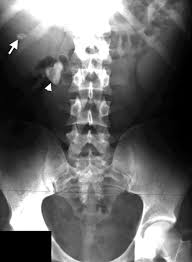

There was no significant difference in measured size between kub and ct p 0 11. Do all kidney stones show up on a kub kidney xray. Combining ultrasound with a kub while not as sensitive or specific as a ct scan does do a pretty good job of picking up clinically significant stones.

A counter argument for using ultrasound in diagnosing of kidney stones is that ureteral stones are usually difficult to visualize with ultrasound and unless they are located at upj or in the distal ureter will not be seen with ultrasound.

Patients with serum creatinine 1 8 mg dl were. The other common study for kidney stones are plain x rays of the abdomen known as kub s which stands for kidney ureter bladder. Patients with serum creatinine 1 8 mg dl were. We then compared accuracy of stone measurement from kub with ct.